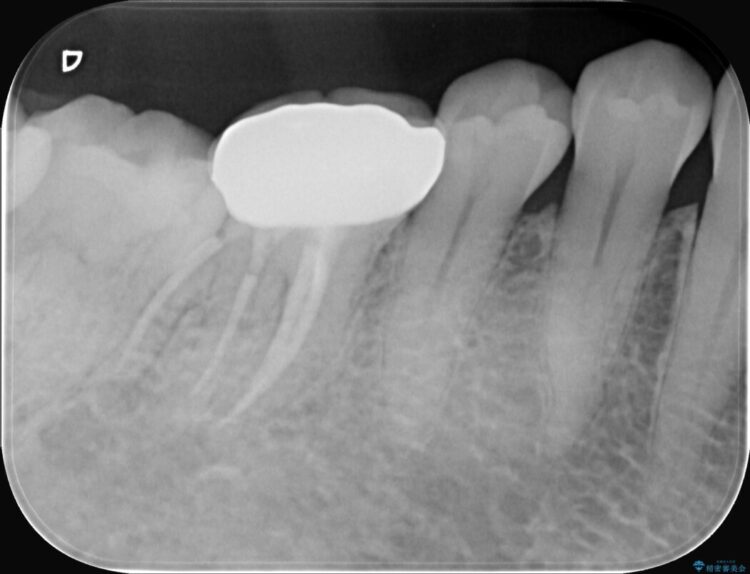

精密検査の結果、根の先に大きな病変が認められますが、根管内が狭窄し湾曲しているため、非常に難易度の高いケースです。

通常の治療器具では奥まで届かず、そのままでは再発や抜歯になるリスクが高いため、マイクロスコープを使用して根の奥まで精密に清掃・殺菌し、歯を残すための治療計画を立てました。

治療では、マイクロスコープで根の中を大きく拡大し、非常に細くなっていた神経の通り道を慎重に見つけ出しました。

次に、根のカーブに沿ってしなやかに曲がるニッケルチタンファイルを使い、根の先まで徹底的に洗浄・殺菌を行いました。汚れを完全に取り除いた後、隙間なくお薬を詰めて密閉しています。

術後の経過は非常に良く、あんなに大きかった膿の袋は消え、健康な骨が再生しているのが確認できました。痛みや腫れも消えて抜歯を免れ、現在は被せ物を入れてしっかりお食事を楽しんでいただけるようになっています。